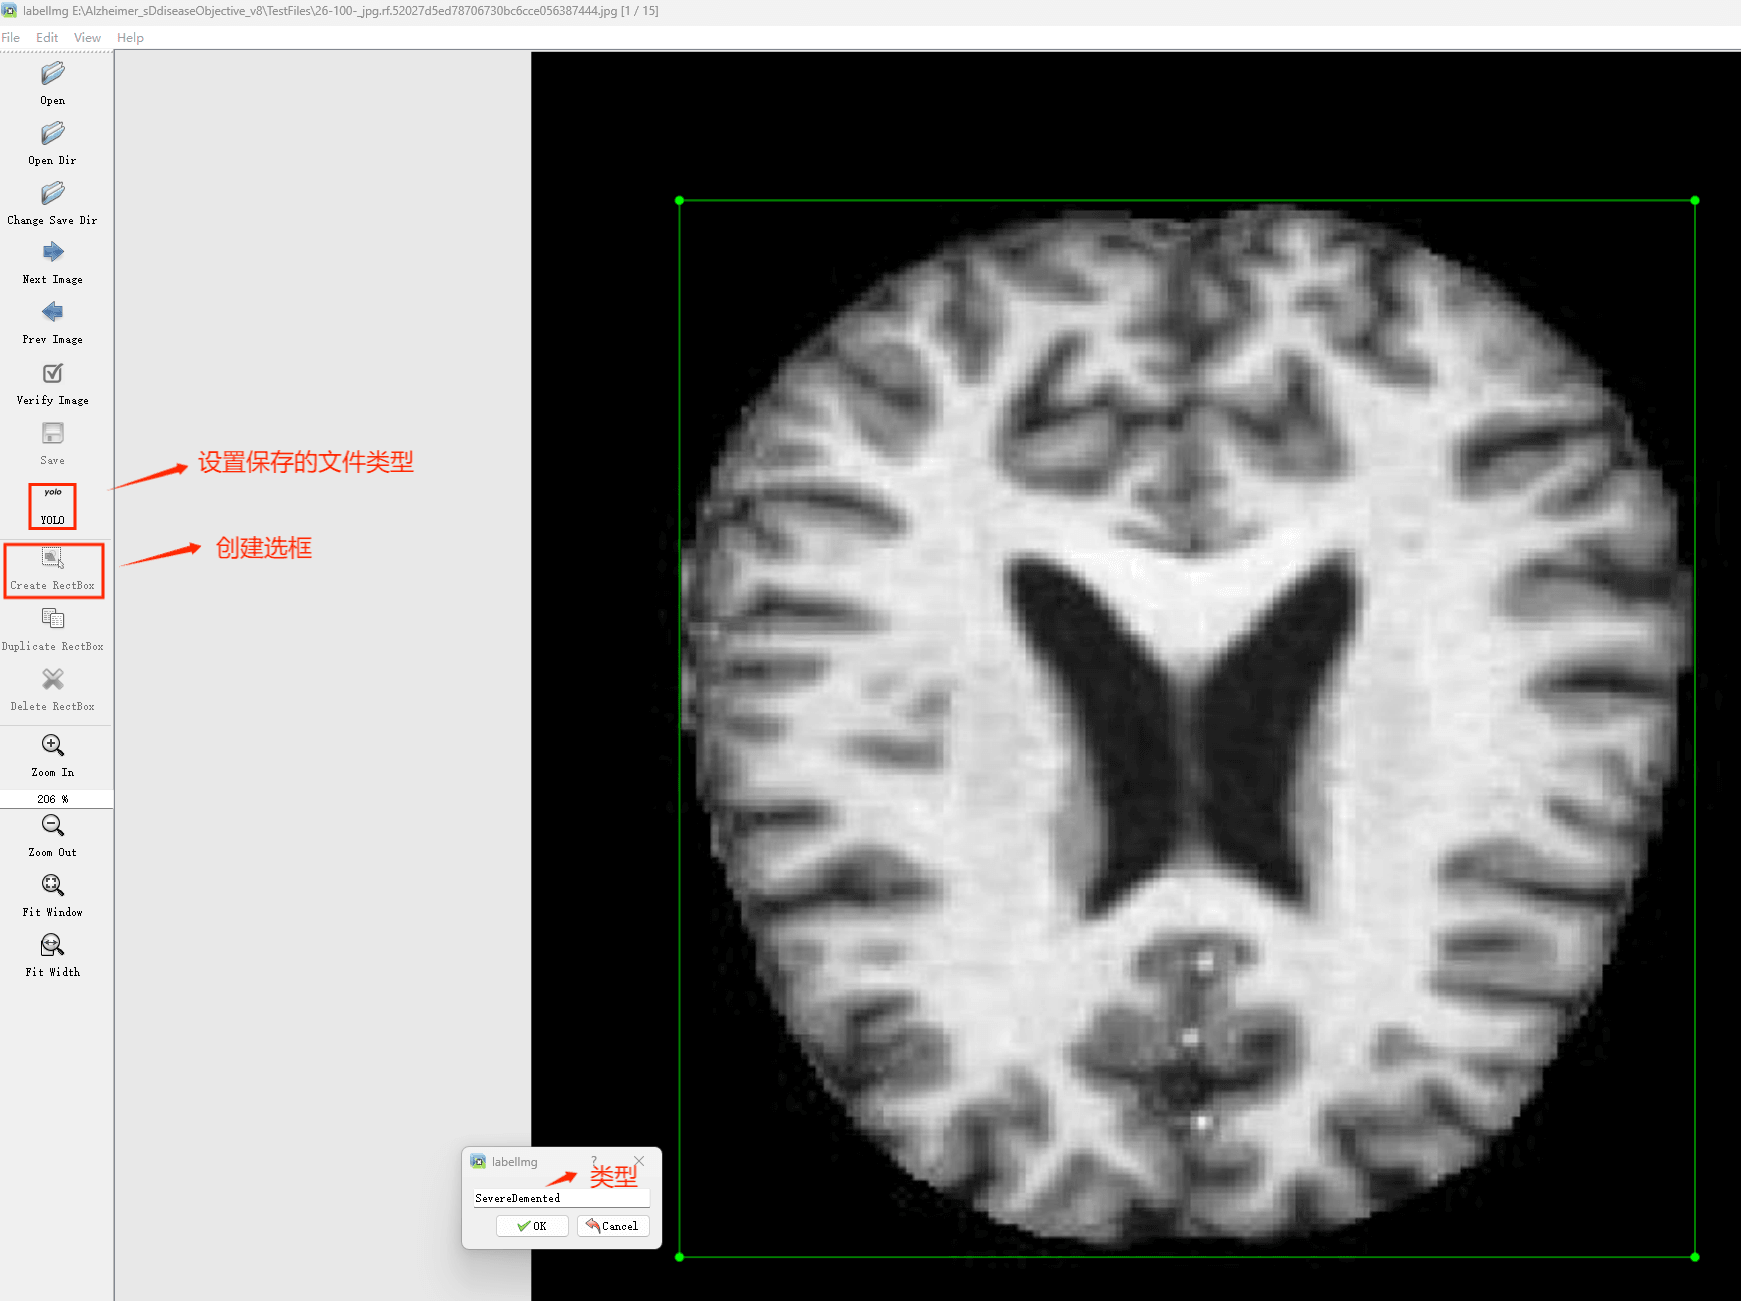

(4)YOLO模式创建标签的样式

存放标签信息的文件的文件名为与图片名相同,内容由N行5列数据组成。

每一行代表标注的一个目标,通常包括五个数据,从左到右依次为:类别id、x_center、y_center、width、height。

其中:

–x类别id代表标注目标的类别;

–x_center和y_center代表标注框的相对中心坐标;

–xwidth和height代表标注框的相对宽和高。

注意:这里的中心点坐标、宽和高都是相对数据!!!

存放标签类别的文件的文件名为classes.txt (固定不变),用于存放创建的标签类别。

完成后可进行后续的yolo训练方面的操作。

2.数据集准备与训练

本研究使用了包含各种老年痴呆症相关图像的数据集,并通过Labelimg标注工具对每张图像中的目标边框(Bounding Box)及其类别进行标注。然后主要基于YOLOv8n这种模型进行模型的训练,训练完成后对模型在验证集上的表现进行全面的性能评估及对比分析。模型训练和评估流程基本一致,包括:数据集准备、模型训练、模型评估。本次标注的目标类别为老年痴呆症,数据集中共计包含3288张图像,其中训练集占2572张,验证集占716张。部分图像如下图所示:

部分标注如下图所示: